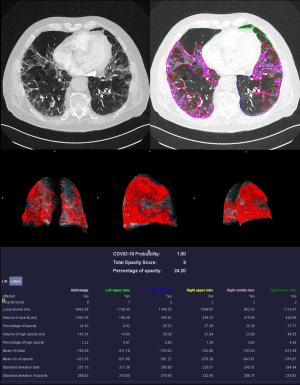

Manual corrections were made after the automatic analysis was completed. Lung lobes were examined and adjusted accordingly. Extensive corrections were required in patients with soft tissue emphysema, where air was confused with lung tissue, and in patients with pleural effusion. Discrepancies between vessel markings and consolidations due to contrast agent were also corrected. Motion artifacts and foreign bodies such as stents and clips were identified, and artifacts appearing as ground-glass opacities or consolidations were removed from the analysis as far as possible. Examples were given in Figures 3,4.

Quantitative CT analysis

The mean probability of COVID-19 in deceased patients was not significantly different (P=0.22) compared to patients that survived, but volume of opacity and high opacity were significantly higher (P=0.007 and 0.04) in deceased patients (Figures 5,6).

In patients who need intensive care treatment with extended lung opacities, the volume of opacity (P<0.001), percentage of opacity (PO) (P<0.001), volume of high opacity (P<0.001), and percentage of high opacity (POH) (P<0.001) were significantly higher. Lobe-specific analysis of COVID-19 pneumonia is provided in Table S3.